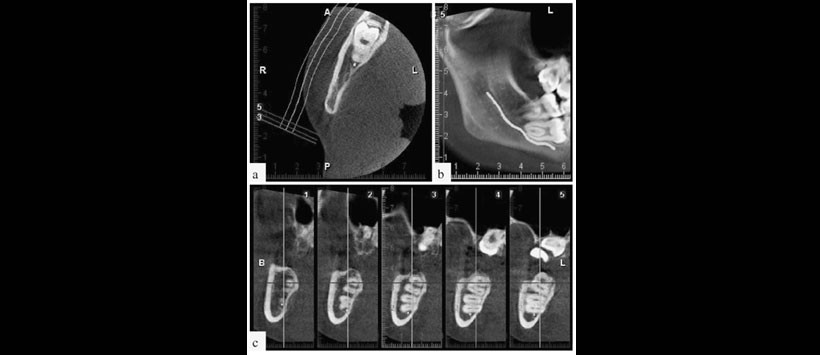

Figura 2: La tomografía computarizada de haz cónico (TCHC) que muestra la proximidad de la pieza 3.7 con el conducto dentario inferior. A (vista axial), B (vista sagital y C (vista transaxial).